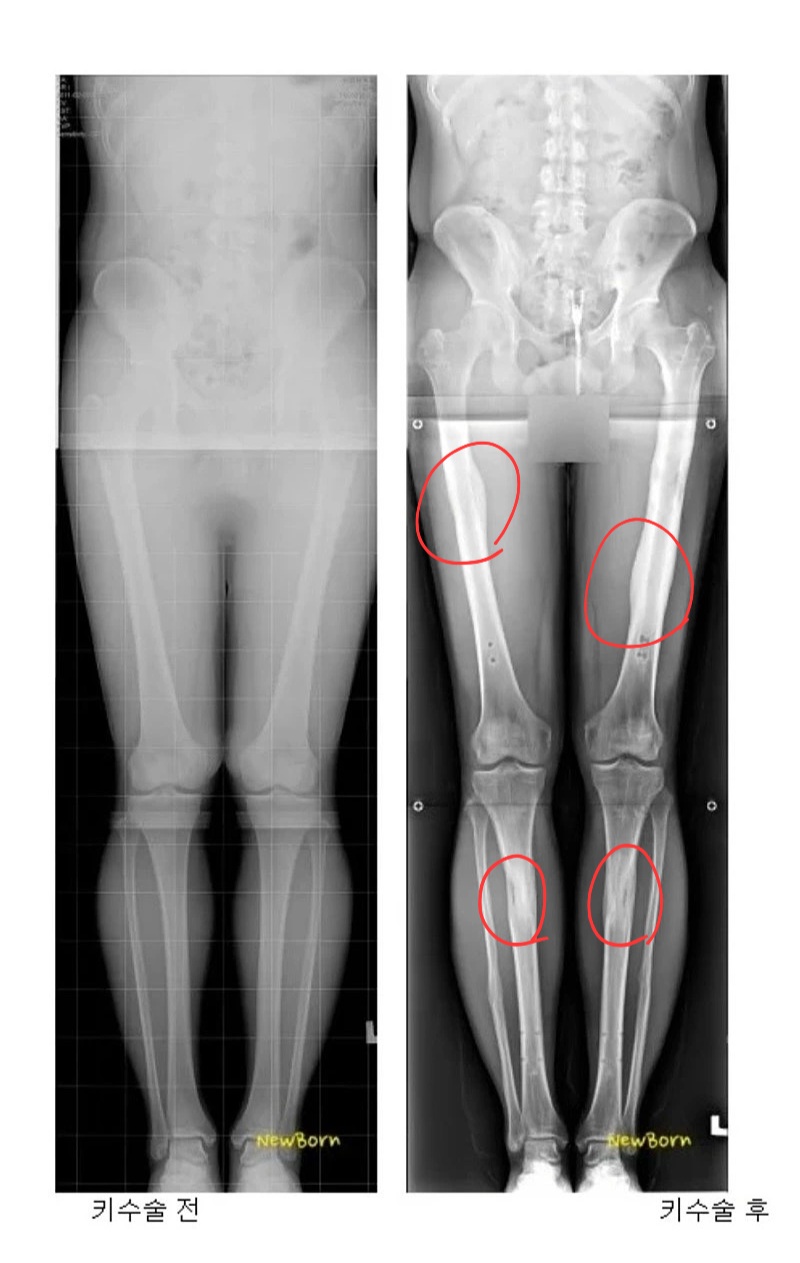

[유머] 어마무시 하다는 키 13cm 연장술...ㅎㄷㄷ;; [82]

5~6cm 도 꽤 신체에 부담가고 영향있을거 같은데 13, 18이면 ㄷㄷ;;

의외로 5~6정도면 영향은 없음. 다만 한번에 늘리는게 아닌 종아리 + 허벅지 각 3cm 정도로 늘리고 재활 활동 빡시게 하고 나면 한 8cm까진 괜찮다더라. 문제는 돈이지. 수술을 총 4번 해야하고 각 수술마다 5천만원 정도 들어가며 + 완치 후 재활까지 길면 2년간 못움직임. 진짜 한이 있는 사람들이 하는 수술임. | 26.01.29 08:17 | | |

아 맞다 수술 총 8번 이구나. 연장 후 뼈에 박아 넣은 구조물 제거 수술까지 하면 총 8번 수술에 치료+ 재활만 3년 반이네. | 26.01.29 08:20 | | |

168이면 5,6센티만 늘려도 충분하지 않나. 늘리지 않고 그냥 살아도 괜찮을키인데 빡세게 늘렸네